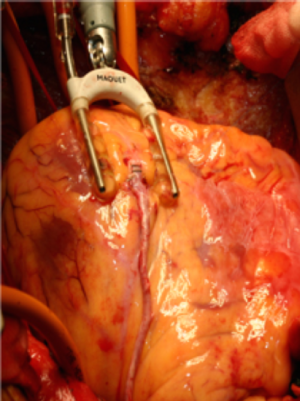

術後のQOL(生活の質)を考慮した僧帽弁形成術(図6・7)

僧帽弁閉鎖不全の手術には、人工弁置換術と自己の僧帽弁を温存・修復する僧帽弁形成術があります。人工弁置換術では、機械弁を使用するとワーファリンの内服を終生必要とし、生体弁は劣化・再手術の問題があります。これに対して、僧帽弁形成術は自己弁を温存するため、劣化の問題もわずかで、心房細動がなければワーファリンは不要で、患者さんのQOLが改善します。

図6 僧帽弁閉鎖不全(前尖の逸脱)

図7 僧帽弁形成術(図8の症例)